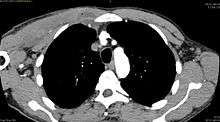

Pyomyositis, also known as tropical pyomyositis or myositis tropicans, is a bacterial infection of the skeletal muscles which results in a pus-filled abscess. Pyomyositis is most common in tropical areas but can also occur in temperate zones.

Pyomyositis is most often caused by the bacterium Staphylococcus aureus.[1] The infection can affect any skeletal muscle, but most often infects the large muscle groups such as the quadriceps or gluteal muscles.[2][3][4]